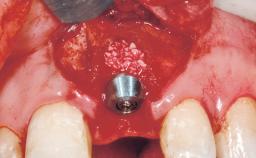

Late Flapless Placement of an Implant in a Maxillary Left Central Incisor Site

A 39-year-old male patient presented with a chief complaint of discomfort and gingival discoloration around his maxillary left central incisor. He was in good general health and was a non-smoker. His past dental history was significant because of the traumatic fracture of tooth 21 in a sporting accident at age 13. Initial dental treatment included endodontic therapy and a full-coverage restoration. The patient became symptomatic 5 years later, when structural failure of the tooth resulted in the dislodgment of the crown. Endodontic retreatment, apical surgery, and post-and-core restoration were performed.

Type of Implants One-Piece

Bone Augmentation Horizontal|Staged

Augmentation Materials Xenogenous|Membrane

Soft Tissue Grafting Simultaneous